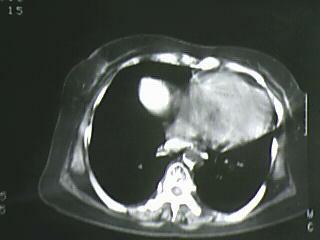

以下是引用bmw011在2009-4-14 19:14:00的发言:[br]右肺继发型肺结核---纵隔淋巴结多发钙化----左肺支扩。支持

以下是引用杀毒软件在2009-4-14 17:52:00的发言:[br]考虑---右肺继发型肺结核---纵隔淋巴结多发钙化----左肺支扩

以下是引用黑白光影在2009-4-14 20:36:00的发言:[br]右肺继发型肺结核;左下慢性支气管炎性病变。